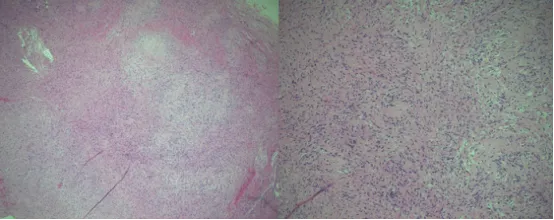

术中发现,病变呈棕黄色,类似橡胶。肿瘤与正常颅骨之间形成了清晰的平面,颅骨内表面仍然完整地覆盖上矢状窦。组织病理学分析显示一个实性包覆的梭形细胞瘤生长在交错的束状结构中,细胞区和低细胞区交替生长,边缘有骨组织碎片。细胞区域含栅栏状排列的细胞核(安托尼A型),交替出现少细胞区域由疏松水肿间质中不规则排列的细胞构成(安托尼B型)。

这些特征共同证实了枕骨内神经鞘瘤的诊断。手术实现了肿瘤的肉眼全切除,术后,利利的神经功能保持完好,并于术后1天出院。随访2个月,利利恢复良好,枕骨创面愈合良好,神经功能完好。这一隐患终被铲除,利利父母彻底放下心来。